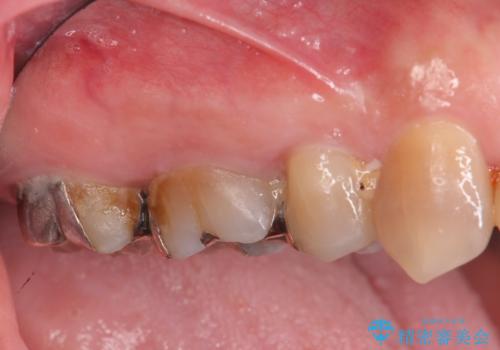

[ 歯周病治療 ] 無症状に進行した歯周病、歯周外科を用いたセラミック治療